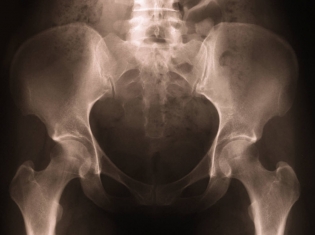

Researchers recently studied a group of patients who had undergone total hip replacement surgery.

For the study, 110 smokers and twice as many non-smokers who had a total hip replacement between 2007 and 2009 were followed for two to six years after undergoing surgery. Patients ranged from 35 to 84 years of age.

The researchers looked at rates of infection, x-rays and how each patient rated function, healing, mobility and pain on the Harris Hip Score scale.